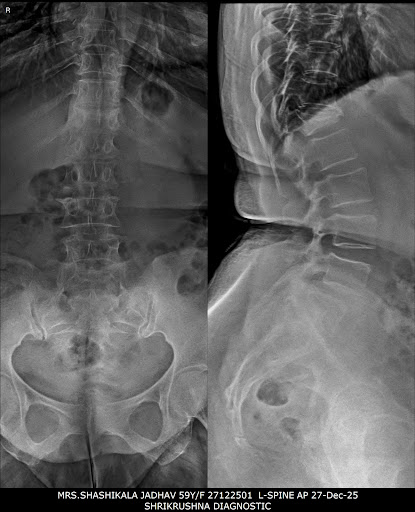

X-ray

Digital Xray

Advanced digital xray

Gallery